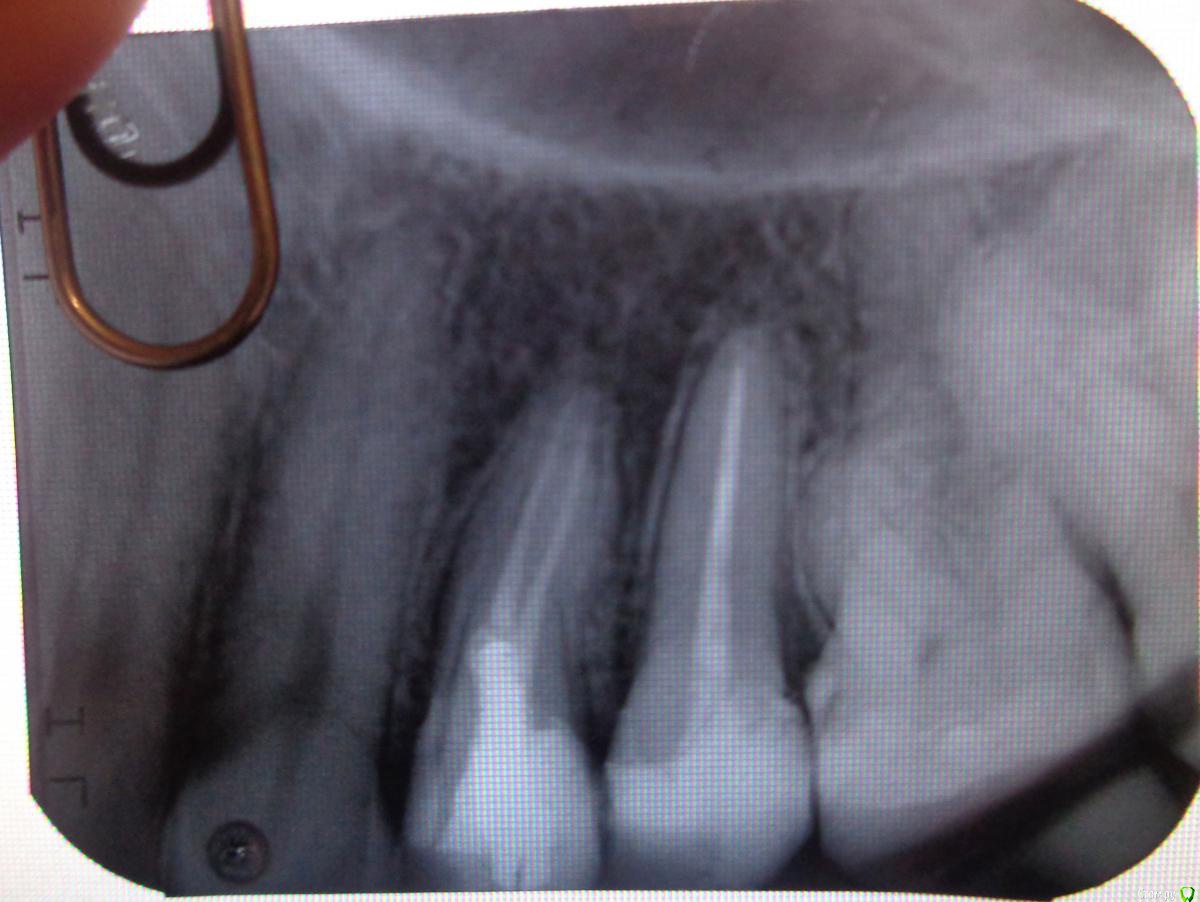

Nadyushka1231 Опубликовано 27 декабря, 2016 Поделиться Опубликовано 27 декабря, 2016 Здравствуйте! Зуб 15 меня совершенно никак не беспокоил, но на осмотре 10 октября врач сказал что есть маленький кариес, но закончилось всё удалением нерва из зуба. 10 дней ныла вся верхняя челюсть, боль отдавала в ухо и в зуб 13 (клык я так думаю болел от укола, т.к. потом мне жаловалась моя знакомая на боль в клыке после удаления нерва у того же врача), при обращении к врачу с этим вопросом (3 раза за 10 дней) на 3й раз меня просто выгнали с тем, что якобы я больна на голову, болеть в зубе нечему. Я пошла к другому врачу в стомат.поликлинику. Из за болей меня отправили на физ. процедуры (лазер+электрофорез). За неделю боль утихла. 25 октября был установлен стекловолоконный штифт и пломба световая. Ночью я поняла что зуб стал снова болеть, но я подумала что болит он от вмешательства. Терпела еще несколько дней, после чего пошла к врачу, но и этот врач мне сказал, что болеть нечему. В середине ноября меня снова отправили на лазер+электрофорез. Потом я пошла к парадонтологу, в надежде на то что боли дает десна, но пародонтолог тоже ничего не увидела, и в целях профилактики отправила меня на лезер на все десна. Зуб как болел так и продолжил болеть. Я поехала в другой город в стомат.клинику. Врач по рентгену тоже ничего не увидел и выписал пропить Ципролет. Я пропила, но боли не прошли. Вот уже прошло 2,5 месяца с момента удаления нерва. Зуб болит при надавливании, при постукивает, болит пол челюсти, боль отдает в область перед ухом. 22 декабря делала рентген этого зуба, но врач снова не видит ничего на рентгене. Сказал что зуб запломбирован нормально, воспаления и кист на корне нет, десна не воспалена. Вот я теперь совсем не знаю что мне делать.... Раньше он меня совсем не беспокоил а теперь уже больше 2 месяцев я мучаюсь с болью и никто не может мне помочь. Соседние зубы при надавливании, постукивании не болят совсем, на холод не реагируют. Боль именно в зубе 15. Посоветуйте пожалуйста, что мне делать?Фото прикрепляю до установки штифта (середина октября), 2 рентген (конец ноября). Последнего рентгена из другого города к сожалению у меня нет, но врач сказал что по последнему рентгену всё нормально. Ссылка на комментарий